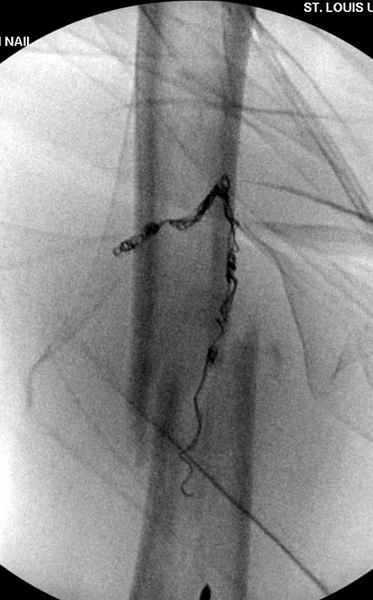

В зависимости от характера опухоли некоторые патологические переломы имеют риск кровотечения во время операции. Множественные литературные данные подтверждают, что надо проявить осторожность при интрамедуллярном остеосинтезе при неизвестных опухолях, особенно где имеется подозрение на Renal Cell Carcinoma. (RCC- hypernephroma) http://www.bonetumor.org/tumors/pages/page64.html

Для предупреждения кровотечения во время рассверливания, за день до операции провели эмболизацию сосудов питающий метастаз. http://radiology.rsnajnls.org/cgi/reprint/150/3/673.pdf (7-11, 12-15-16)